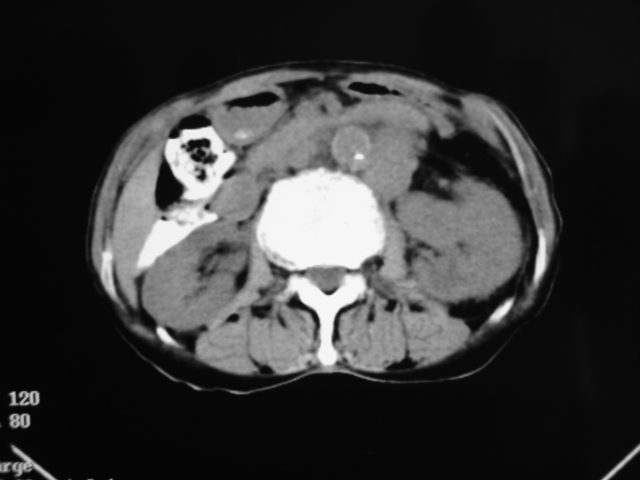

同事奶奶,73岁,腹痛一年,夜晚较重,潜血+++,拒绝增强,考虑左肾ca并腹膜后转移;请各位老师帮忙看看,谢谢!

左肾癌侵及输尿管上段,腹膜后多发淋巴结转移,脾脏钙化灶。至于潜血+++,要考虑消化道病变,本次ct片肠腔未见明显异常。

1)考虑左肾癌侵犯肾盂并腹膜后淋巴结转移。2)脾脏钙化灶。

考虑左肾癌侵犯肾盂并腹膜后淋巴结转移。